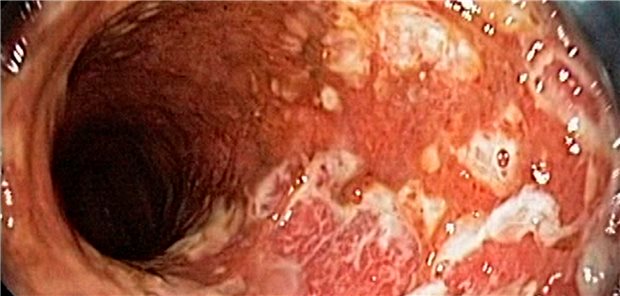

Eine intensivierte Therapie bei Morbus Crohn und Colitis ulcerosa ist noch kein Garant für verbesserte Langzeitergebnisse. Das stellten Experten beim Gastro Update klar.